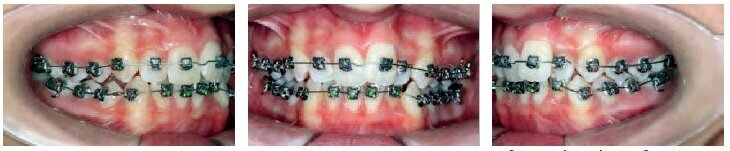

VISIT NO 3: 10 MONTHS

Ten months into the treatment, the 014 archwires were kept on, and both arches showed excellent progress in terms of leveling-alignment. Crowding was fully resolved.

A panorex was done to confirm the proper placement of the initial brackets.

Only the maxillary central incisors (whose roots showed significant proclination) were rebonded with standard torque brackets.

Both arches were fitted with 16x25 CN archwires, and the bite turbos were gradually reduced.

VISIT NO 4: 14 MONTHS

It was as if time was doing the work for us. After just 2 visits over 14 months, a remarkable correction was observed in all 3 orders.

Nonetheless, 13 was repositioned to provide a more gingival placement and to correct tipping (see the panorex taken 4 months earlier, which shows an excessive tip-back of this tooth).

For the maxillary arch, the 16x25 CN archwire was replaced with an 18x25 CN archwire, and the mandibular arch was fitted with a 17x25 TMA archwire. The patient was also required to wear vertical intercuspation elastics on the upper canines.

The bite turbos were removed completely during this appointment.